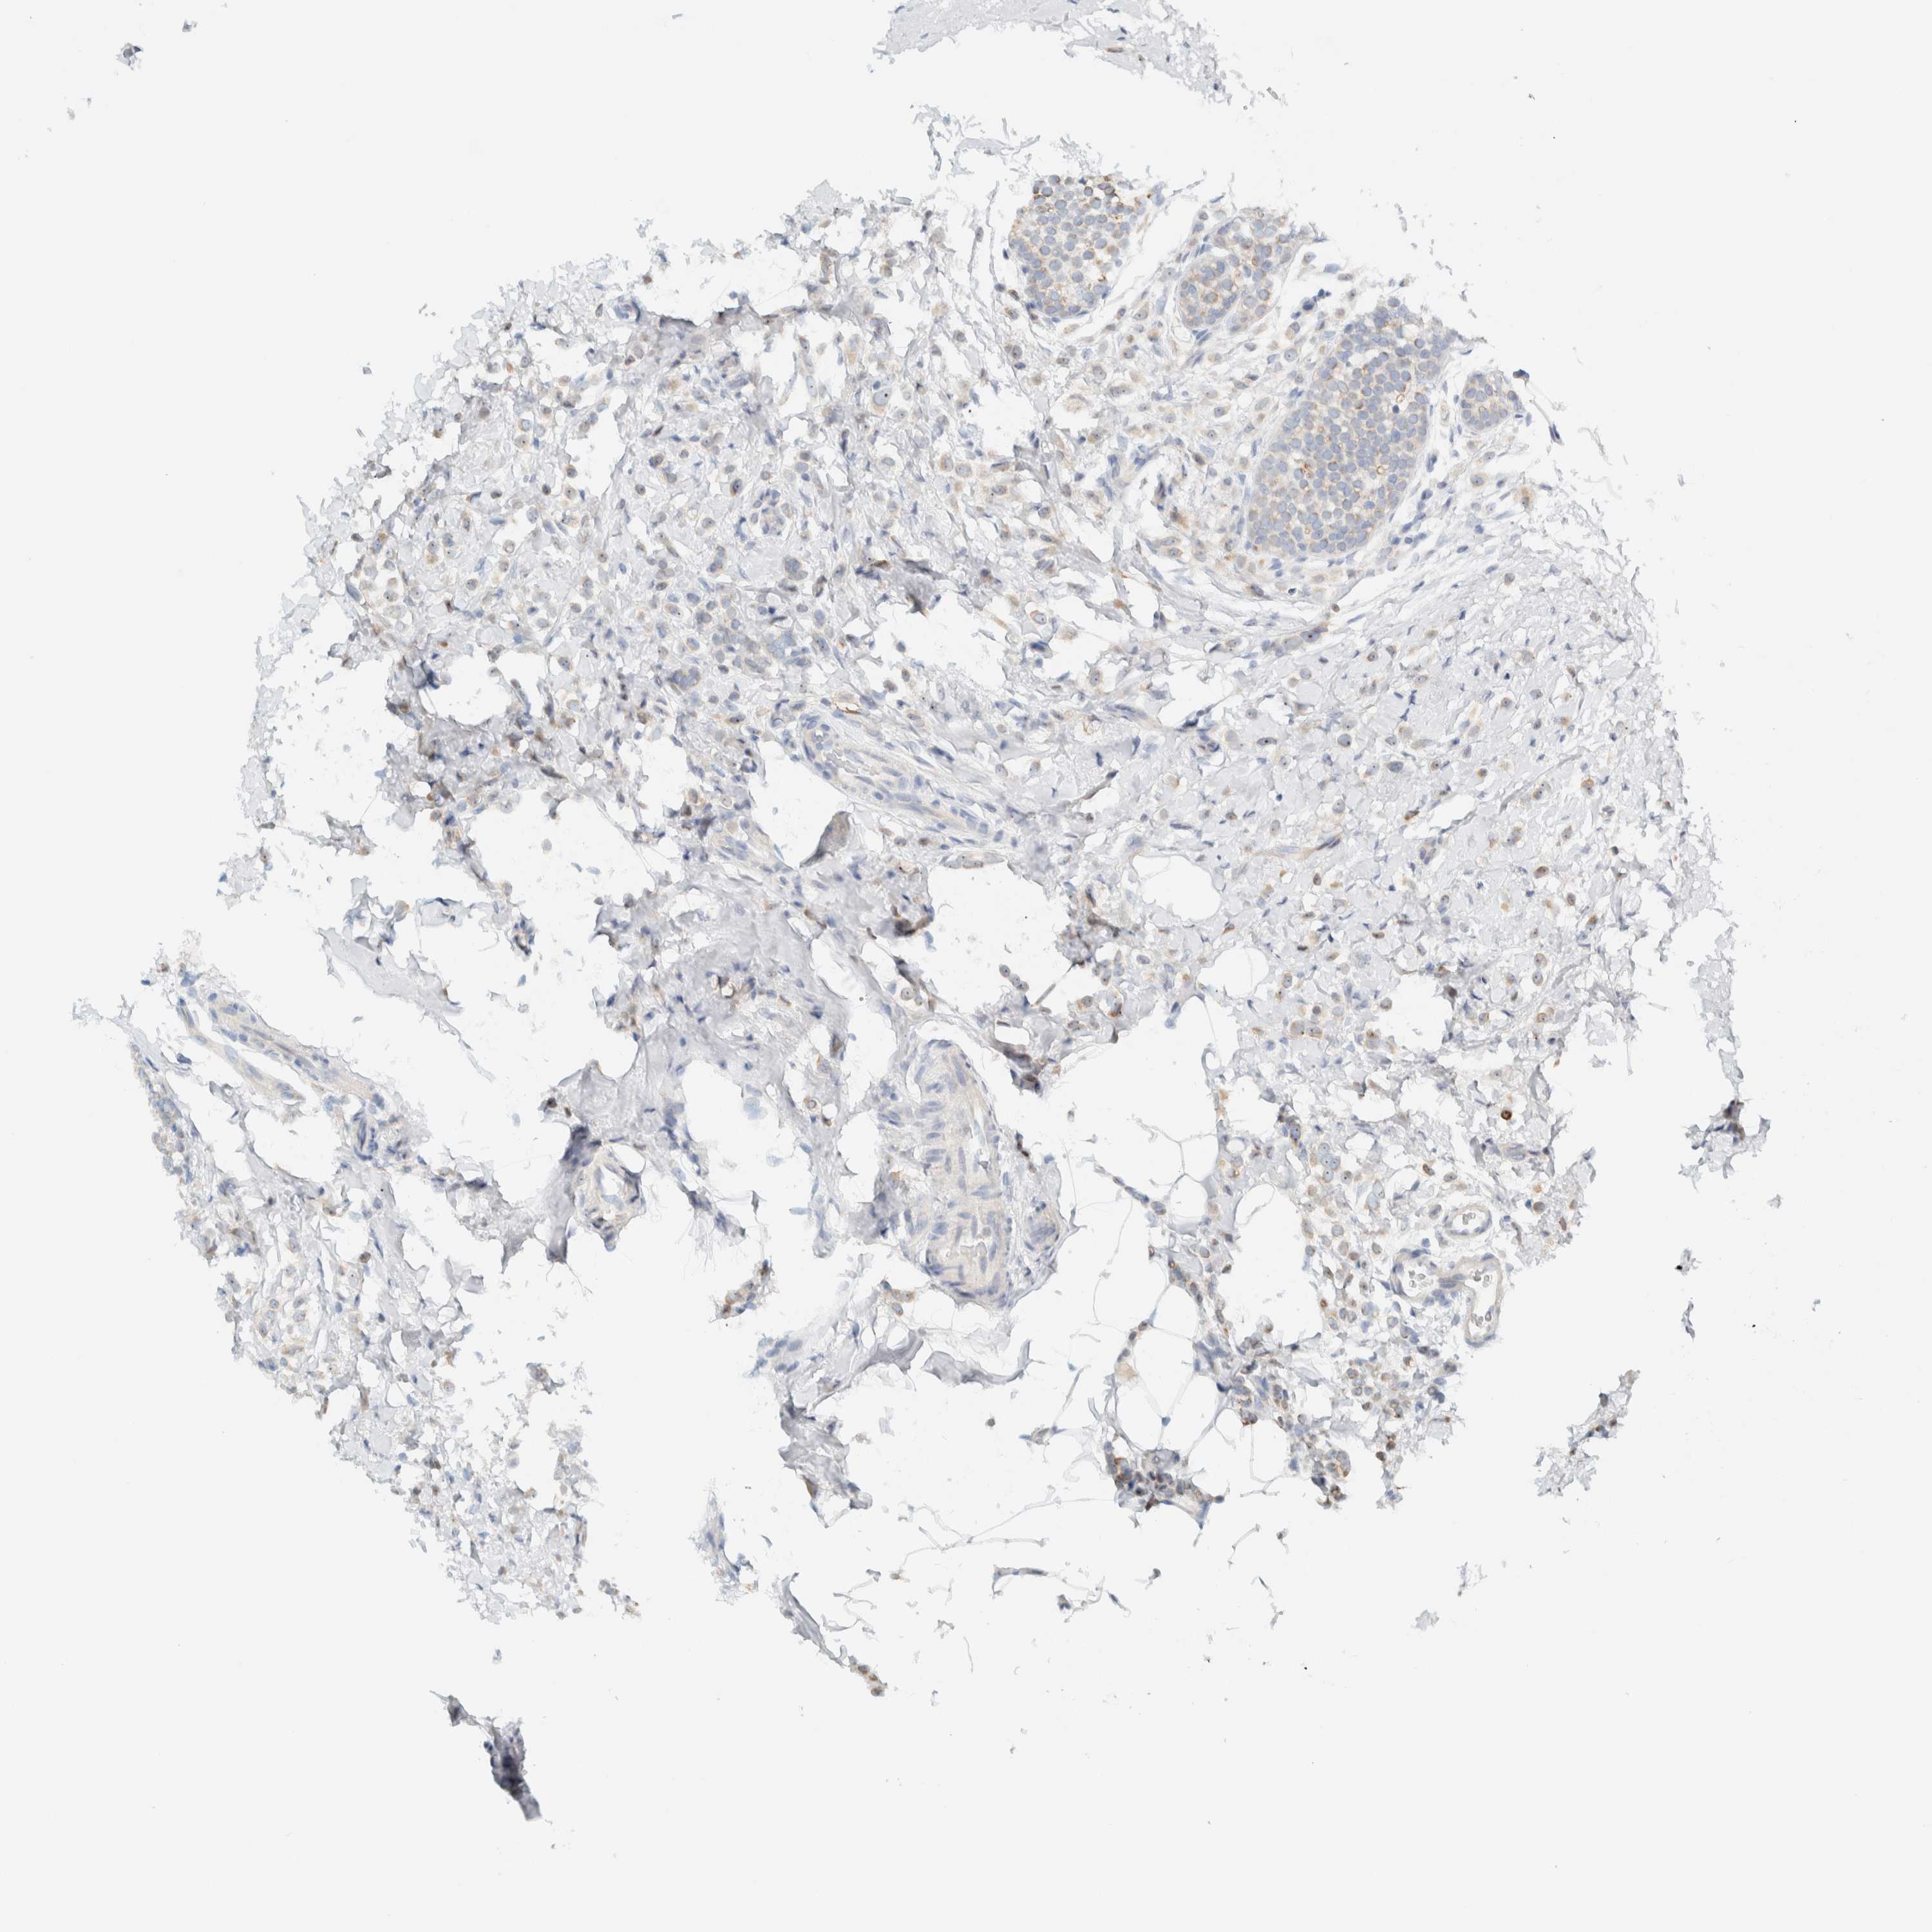

CANCER BREAST CANCER Show tissue menu

BRCA TCGA BRCA VALIDATION PROTEIN EXPRESSION